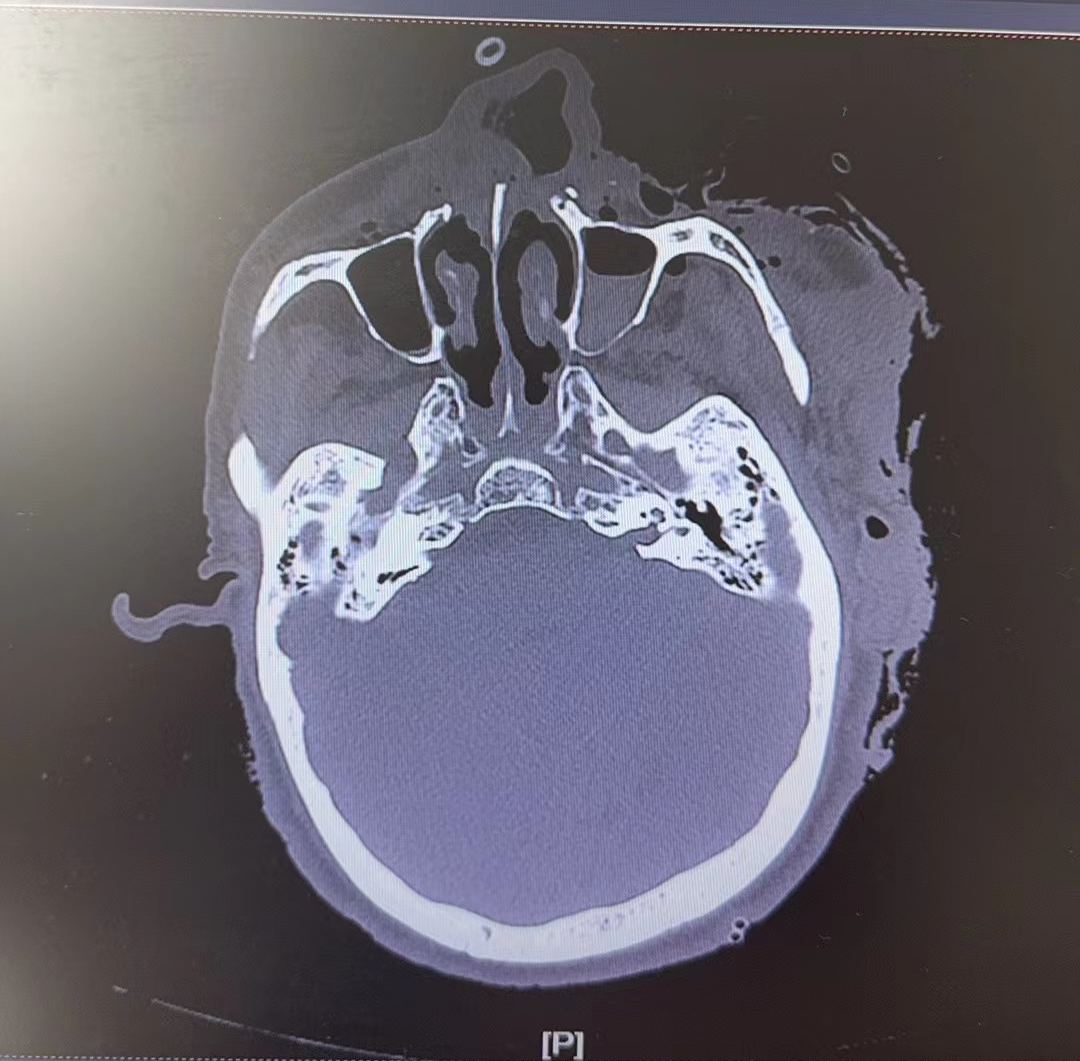

那天,71歲的劉大爺被黑熊襲擊。他的鼻骨、上頜骨廣泛骨折,骨骼塌陷。面部皮膚撕脱,軟組織廣泛移位、有深部碾挫傷,一側鼻孔挪到面頰位置。

8月7日清晨,71歲劉大爺上山採松茸,遭遇黑熊襲擊。最嚴重的傷主要集中在面部。圖源/四川省人民醫院

圖源/受訪者提供

屆時,診療團隊會針對其頭面部進行CT三維重建,獲得數據、製作模型、模擬手術過程。崔瑋計劃採用鈦合金等高分子人工材料,填補劉大爺缺失的組織等。通俗理解,就是給房子換根大梁,支撐起主要結構,以明顯改善面部畸形。